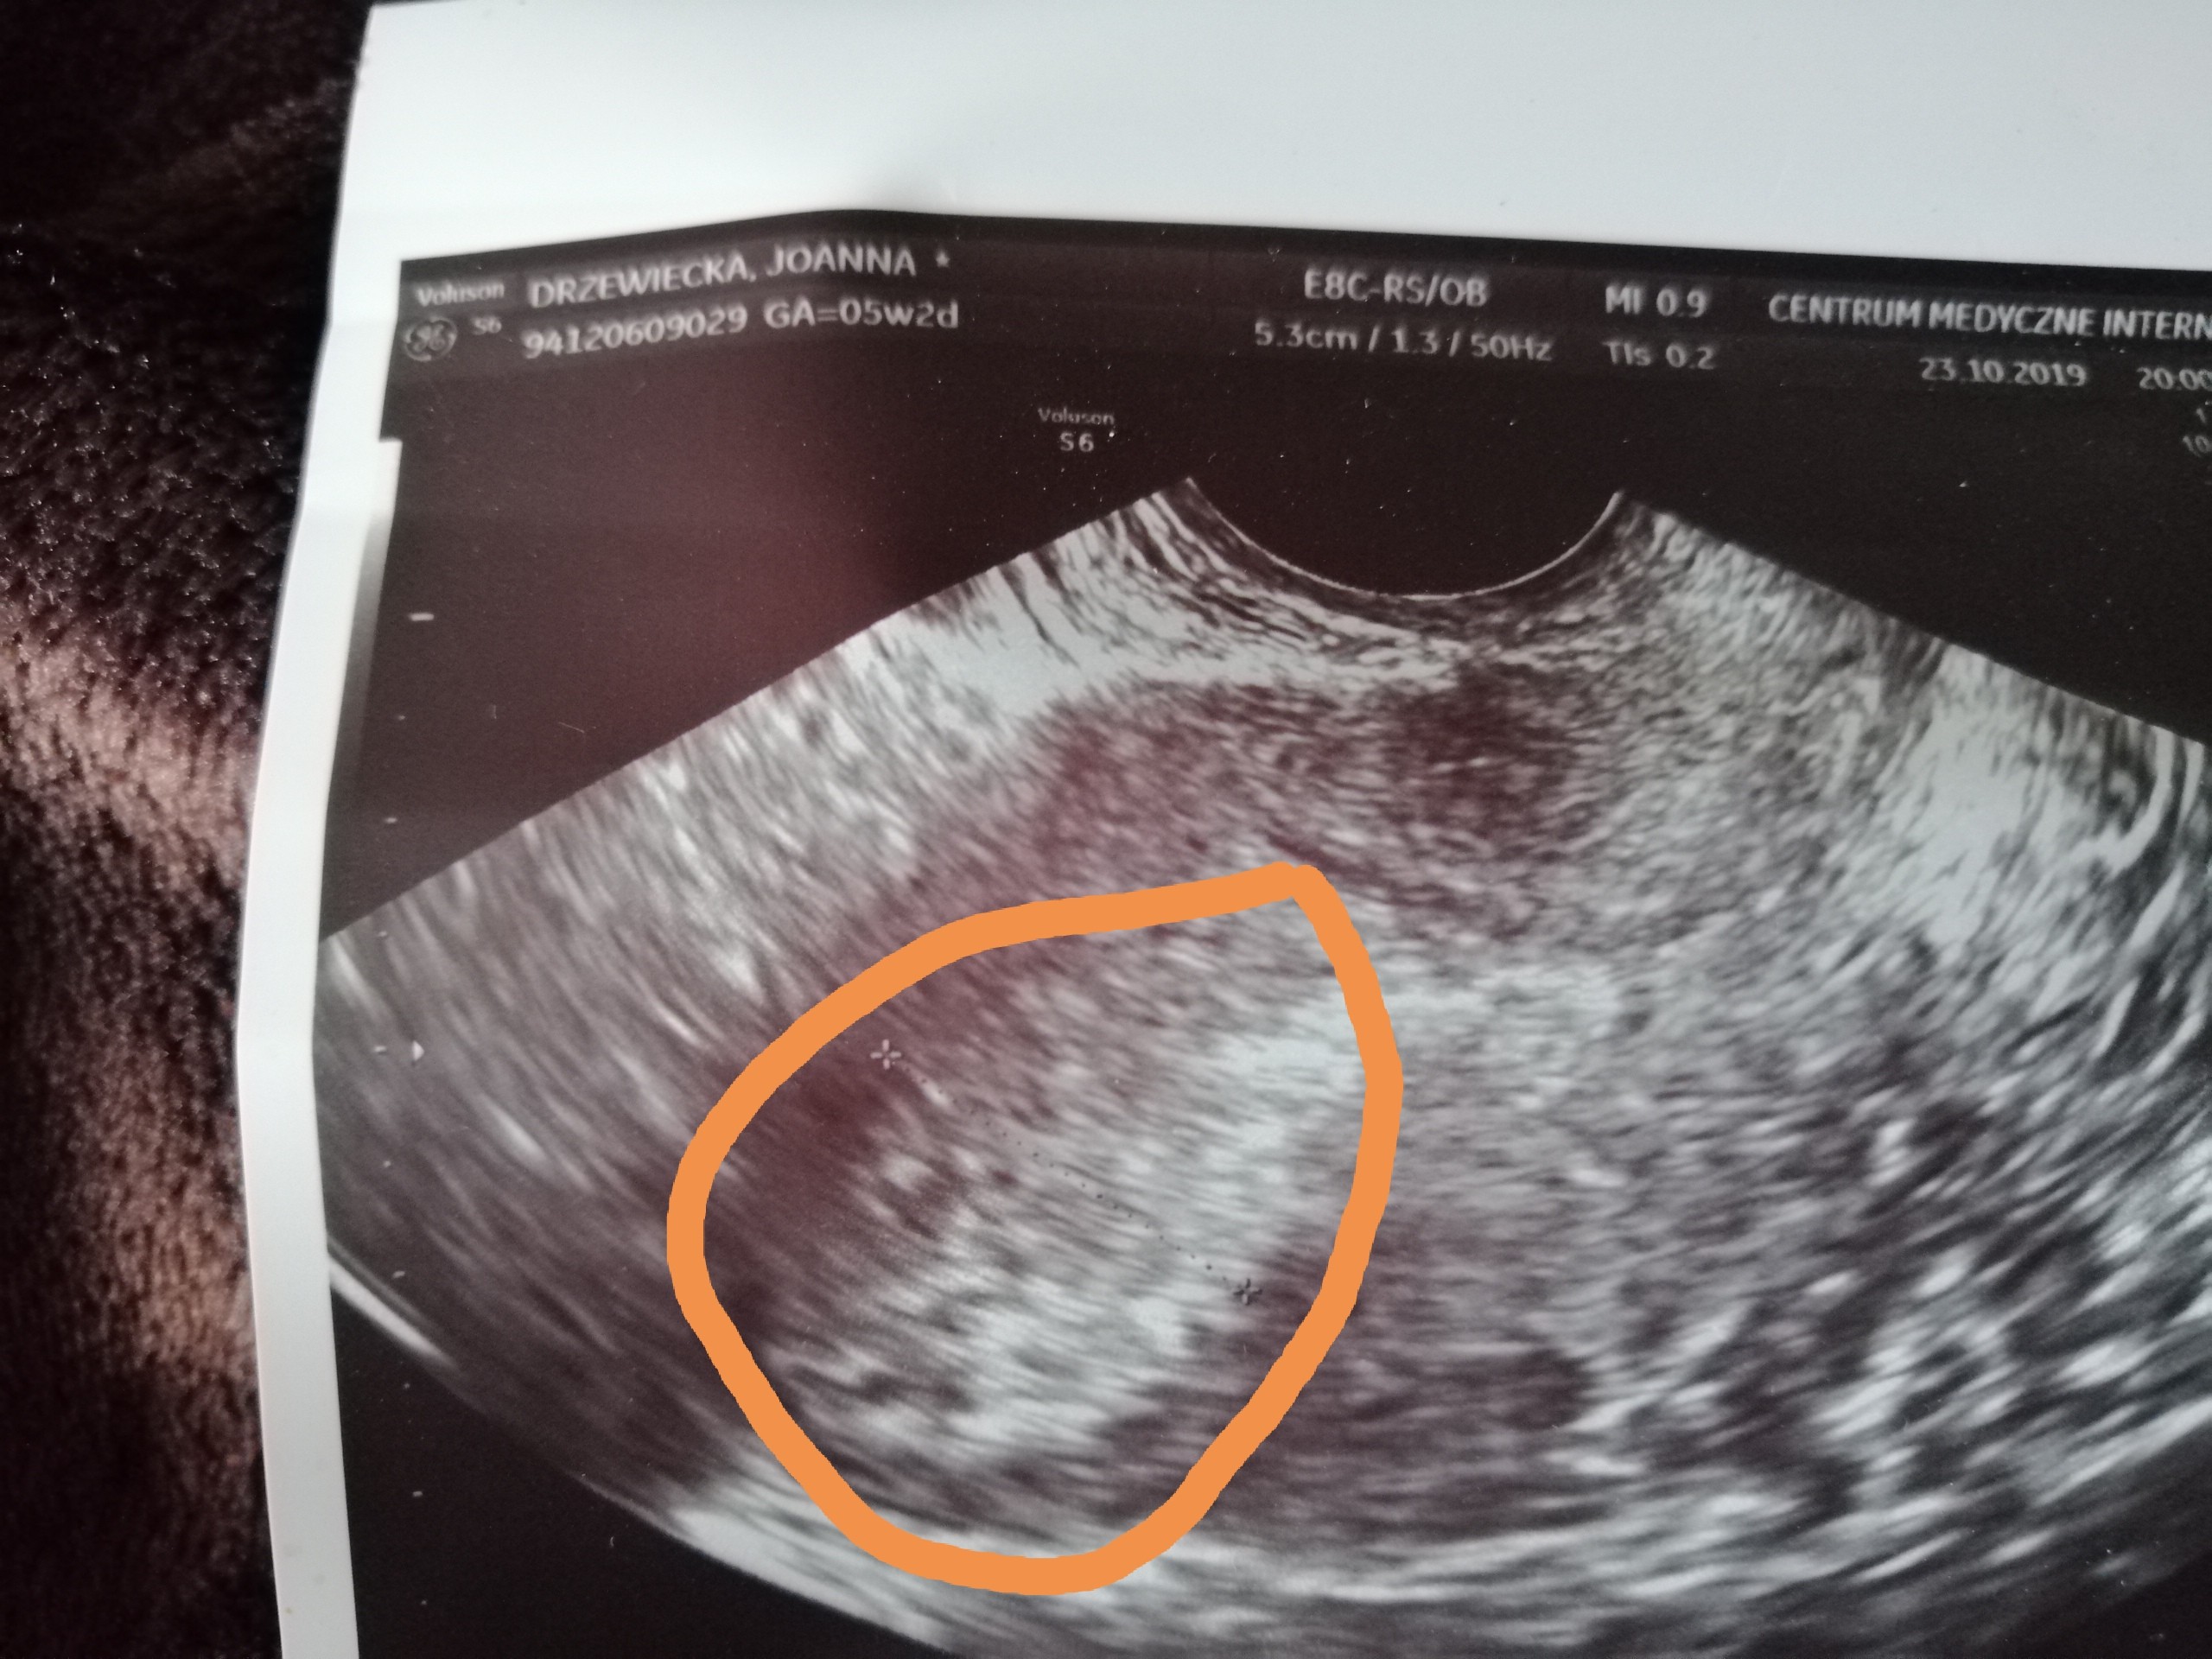

Dziewczyny, według ostatniej miesiączki w dniu usg czyli 23 października ciąża powinna mieć 5 tygodni i 2 dni. Niestety w macicy nie bylo nic widać oprócz ogniska implantacji... (to też watpliwy obraz czy to napewno to)

Czy któraś z Was tak miała i ciąża okazała się młodsza niż w rzeczywistości? 16.10 miałam lekkie jednorazowe plamienie, był to dzien w którym wykonałam test ciazowy. Wyszedł pozytywny lecz kreska była blada.

Pierwsza beta 17.10 - 70

Druga beta 21.10 - 285

Trzecia beta 23.10 - 785

Czwarta beta 25.10 - 2050

Czy mogę mieć jeszcze jakaś nadzieję że będzie ok? Następne usg 6 listopada.

Pęcherzyk widać przy becie ok.1000 w zależności od sprzętu lekarza i indywidualnych cech ciąży. Więc skoro Ty miałaś 700 to obstawiam że za wcześnie poszłaś i już np. w tym momencie jakbyś się wybrała to pęcherzyk by był. Także bez stresu, na razie mieścisz się we wszystkich widełkach a wizyta u ginekologa prawdopodobnie była po prostu zbyt szybka :)